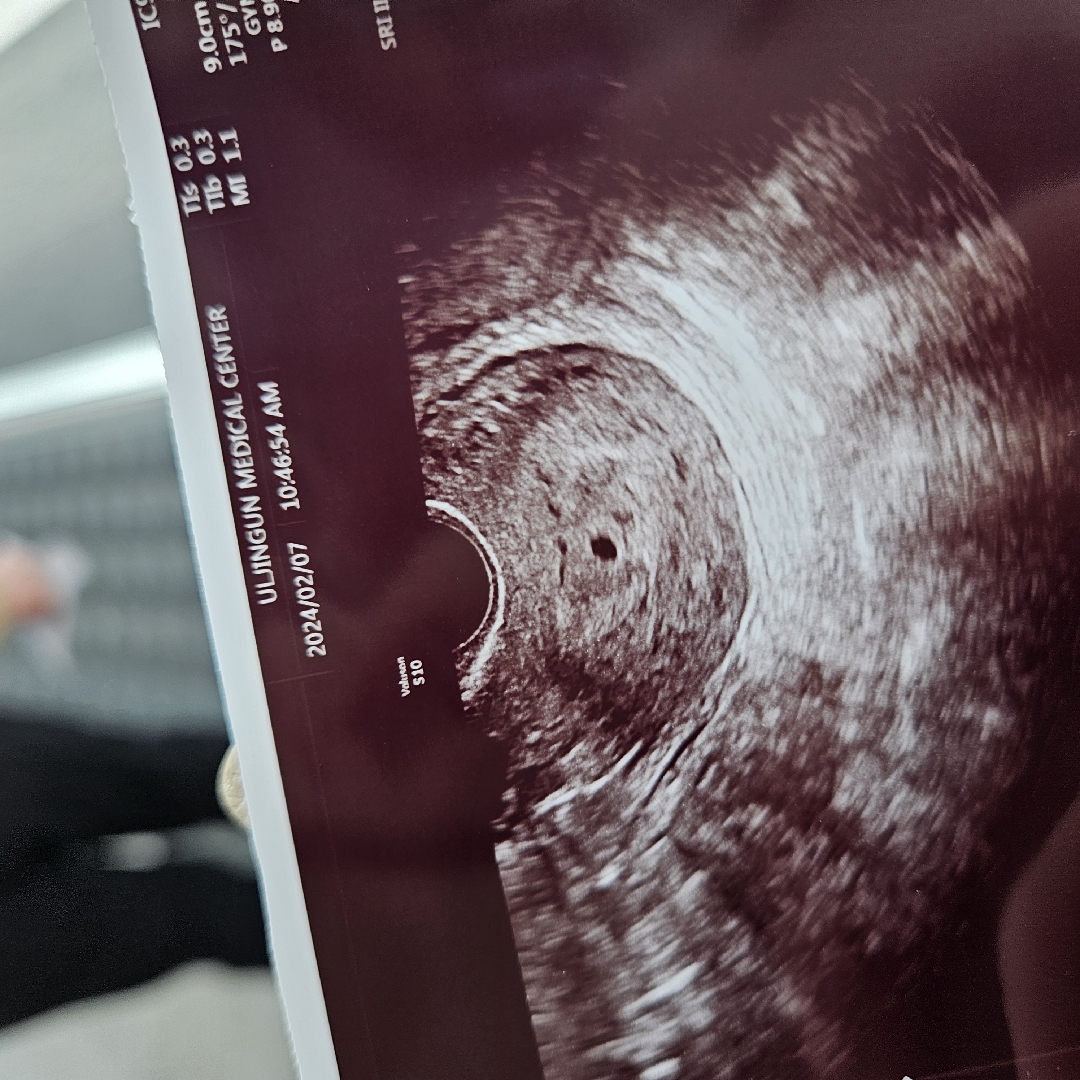

5주0일 초음파!

5주0일차 아기집 보고왔어요! 이틀전만해도 안보였는데 이틀만이 뚝딱 집지은 쿠리야..대단하구나! 잘착상했다하네요 다행입니다요 🥹💗